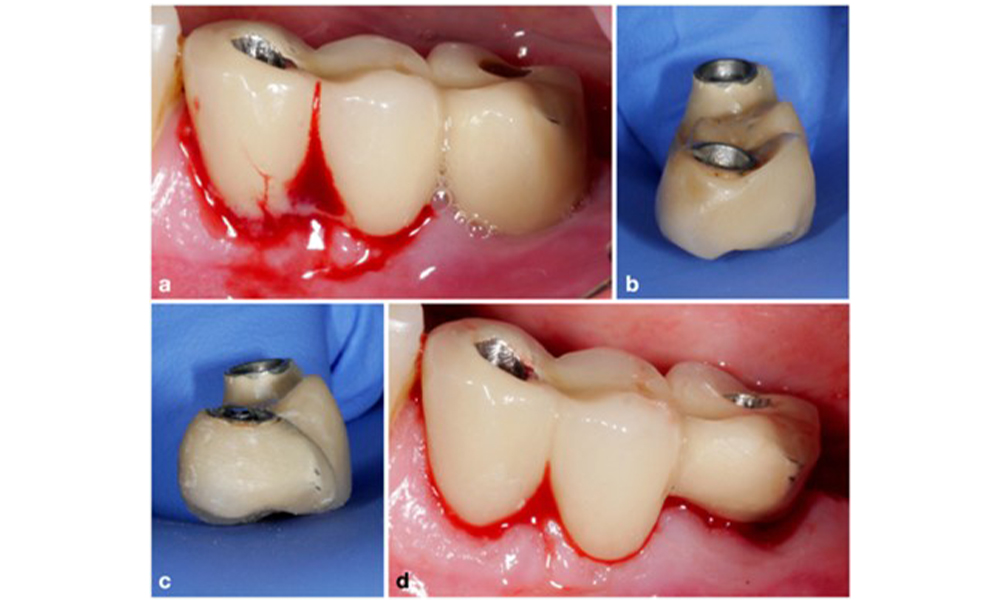

The World Workshop on the Classification of Periodontal and Peri‐Implant Diseases and Conditions from 2017 established diagnostic criteria for peri-implant mucositis and peri-implantitis (Renvert et al. 2018). Peri-implant mucositis is defined as (1) presence of inflammation around the implant (i.e., redness, swelling, line or drop of bleeding within 30 seconds of probing), combined with (2) no additional bone loss after initial healing (figure 1).

Implant in position 26 with peri-implant mucositis (a–c). The probing depth value of 5 mm (b) remains consistent with the measurement taken a few weeks after placing the prosthetic reconstruction. There is bleeding on probing (c) but the radiograph indicates no additional bone loss beyond what is expected for marginal bone remodelling (d).

Figure 1. Implant in position 26 with peri-implant mucositis (a–c). The probing depth value of 5 mm (b) remains consistent with the measurement taken a few weeks after placing the prosthetic reconstruction. There is bleeding on probing (c) but the radiograph indicates no additional bone loss beyond what is expected for marginal bone remodelling (d).

Peri-implantitis is identified by (1) signs of inflammation similar to mucositis, (2) radiographic evidence of bone loss after initial healing and (3) an increase in probing depth compared to measurements taken shortly after placing the prosthetic reconstruction (figure 2). In the absence of previous radiographs, radiographic bone level of ≥ 3 mm along with bleeding on probing and probing depths ≥ 6 mm, indicates peri‐implantitis.